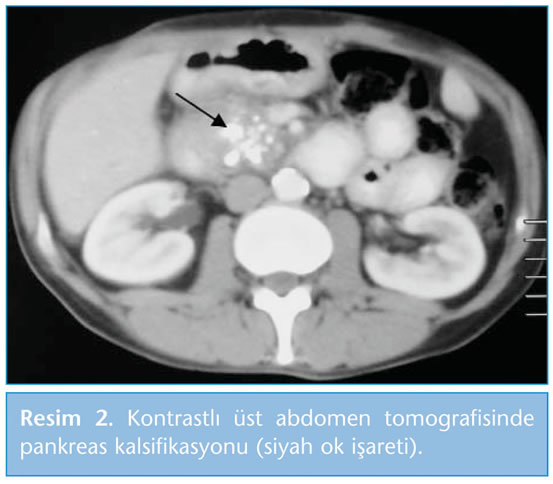

b. Kontrastlı abdomen tomografisi: Kronik pankreatit şüphesi olan hastalarda ilk olarak istenmesi gereken radyolojik incelemedir. Sensitivitesi %75 ile %90 arasında değişirken spesifisitesi %85'tir. Kalsifikasyon, psödokist, tromboz, psödoanevrizma, nekroz ve atrofi olup olmadığını saptamada yararlıdır  (Resim 2) (2,5,19,26).